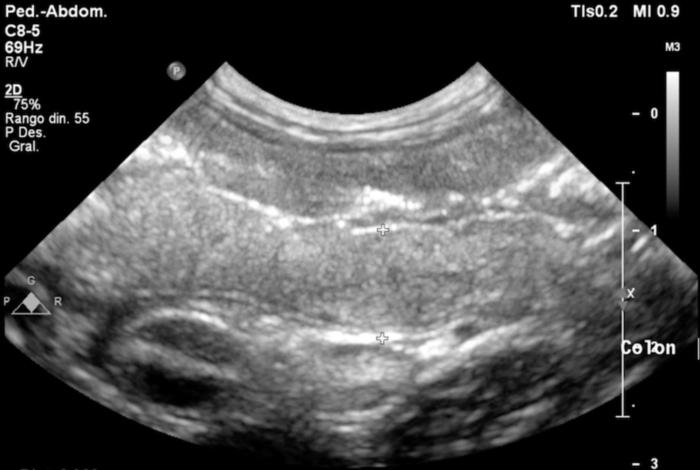

La ecografía abdominal mostró un engrosamiento marcado de la pared del colon, especialmente en el ciego y el colon descendente, con pérdida de la diferenciación normal de capas (Figura 2-3). También se observó linfadenomegalia mesentérica y una pequeña cantidad de líquido libre abdominal (no muestreable). Estos hallazgos reforzaron la sospecha de enfermedad inflamatoria intestinal, principalmente afectando al intestino grueso.